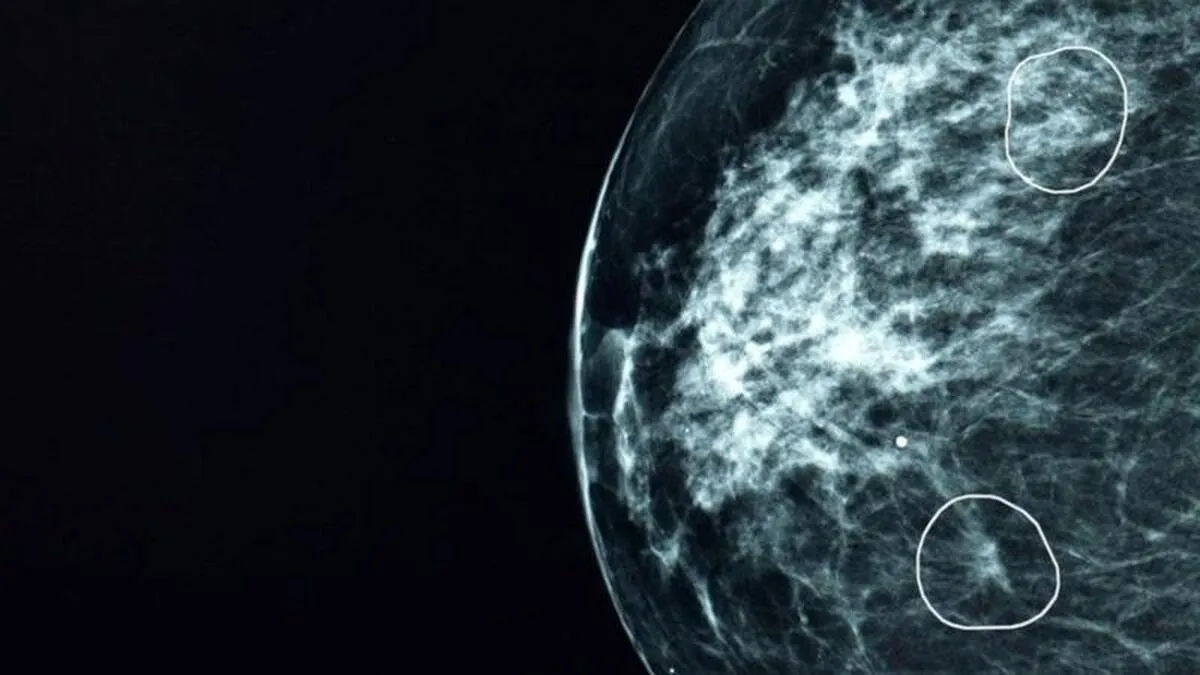

هوش مصنوعی سرطان پستان ۱۱ زن را تشخیص داد

یک مرکز بیمارستانی در اسکاتلند با هوش مصنوعی نشانه‌های ناپیدای سرطان پستان را که از از چشم پزشکان دور مانده بودند، در ۱۱ زن تشخیص داد.

زی‌سان: این فناوری هوش مصنوعی برای تشخیص سرطان پستان که میا نام دارد، در یک برنامه آزمایشی در کنار پزشکان برای بررسی ماموگرافی بیش از ده هزار زن به کار گرفته شد که بیشترشان سرطان نداشتند. میا نه فقط با موفقیت همه کسانی را که علائم سرطان داشتند شناسایی کرد، بلکه ۱۱ زن را هم پیدا کرد که سرطانشان از چشم پزشکان مخفی مانده بود.